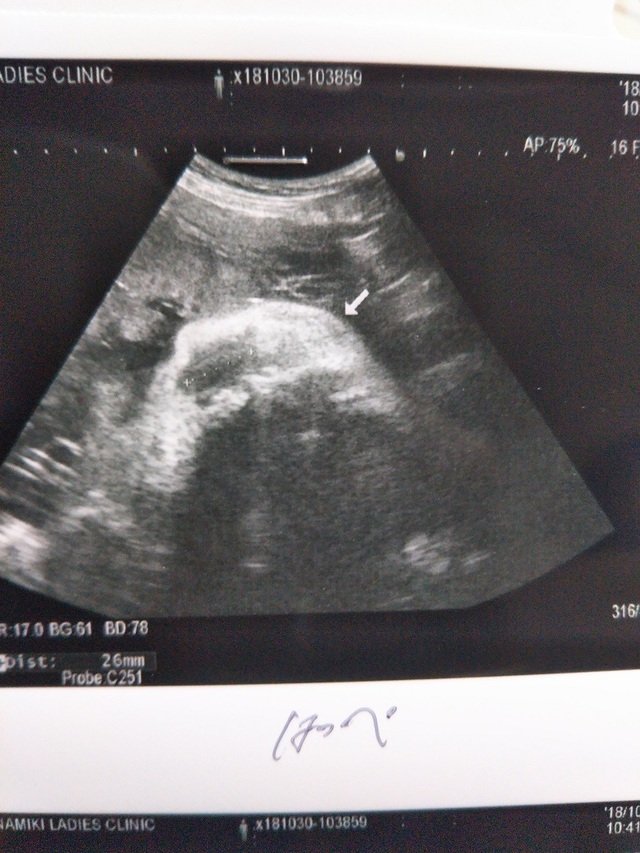

38週4日(38w4d・男の子)|きたうらりさ さん(27歳)

エコー写真撮影時のエピソード:

お腹も大きくなって食欲は増す一方で体重も増える一方。先生からは注意され頭も下がってきてないから頑張ってウォーキングしていた頃。パパとは離れていたので電話しながら色々話して楽しみにしてたなー。臨月にしてようやく初めてまともに顔がエコーで見れて嬉しかった。